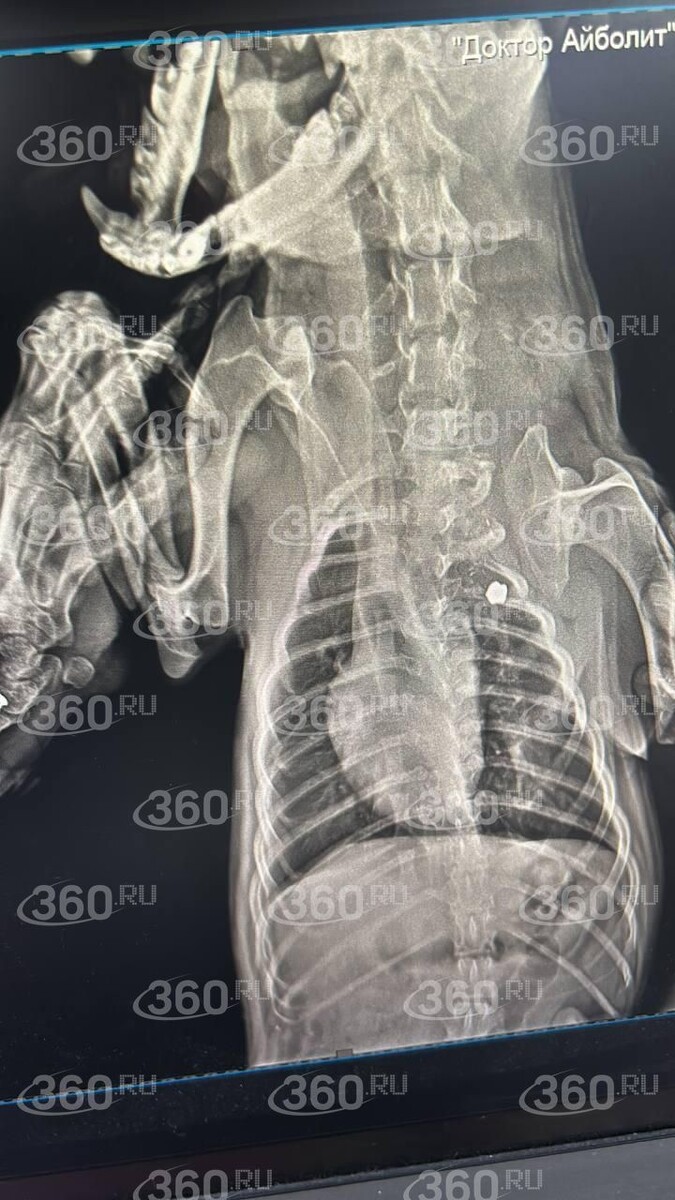

Она отвезла пса в ветеринарную клинику, при обследовании специалисты нашли пулю.

«Сделали рентген. Пуля в труднодоступном месте, оперировать не стали», — добавила собеседница 360.ru.